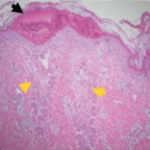

Treated skin histology

Immediately after treatment – Fractional laser energy creates micro-ablated columns to stimulate cellular regrowth. The surrounding healthy tissue promotes rapid healing.